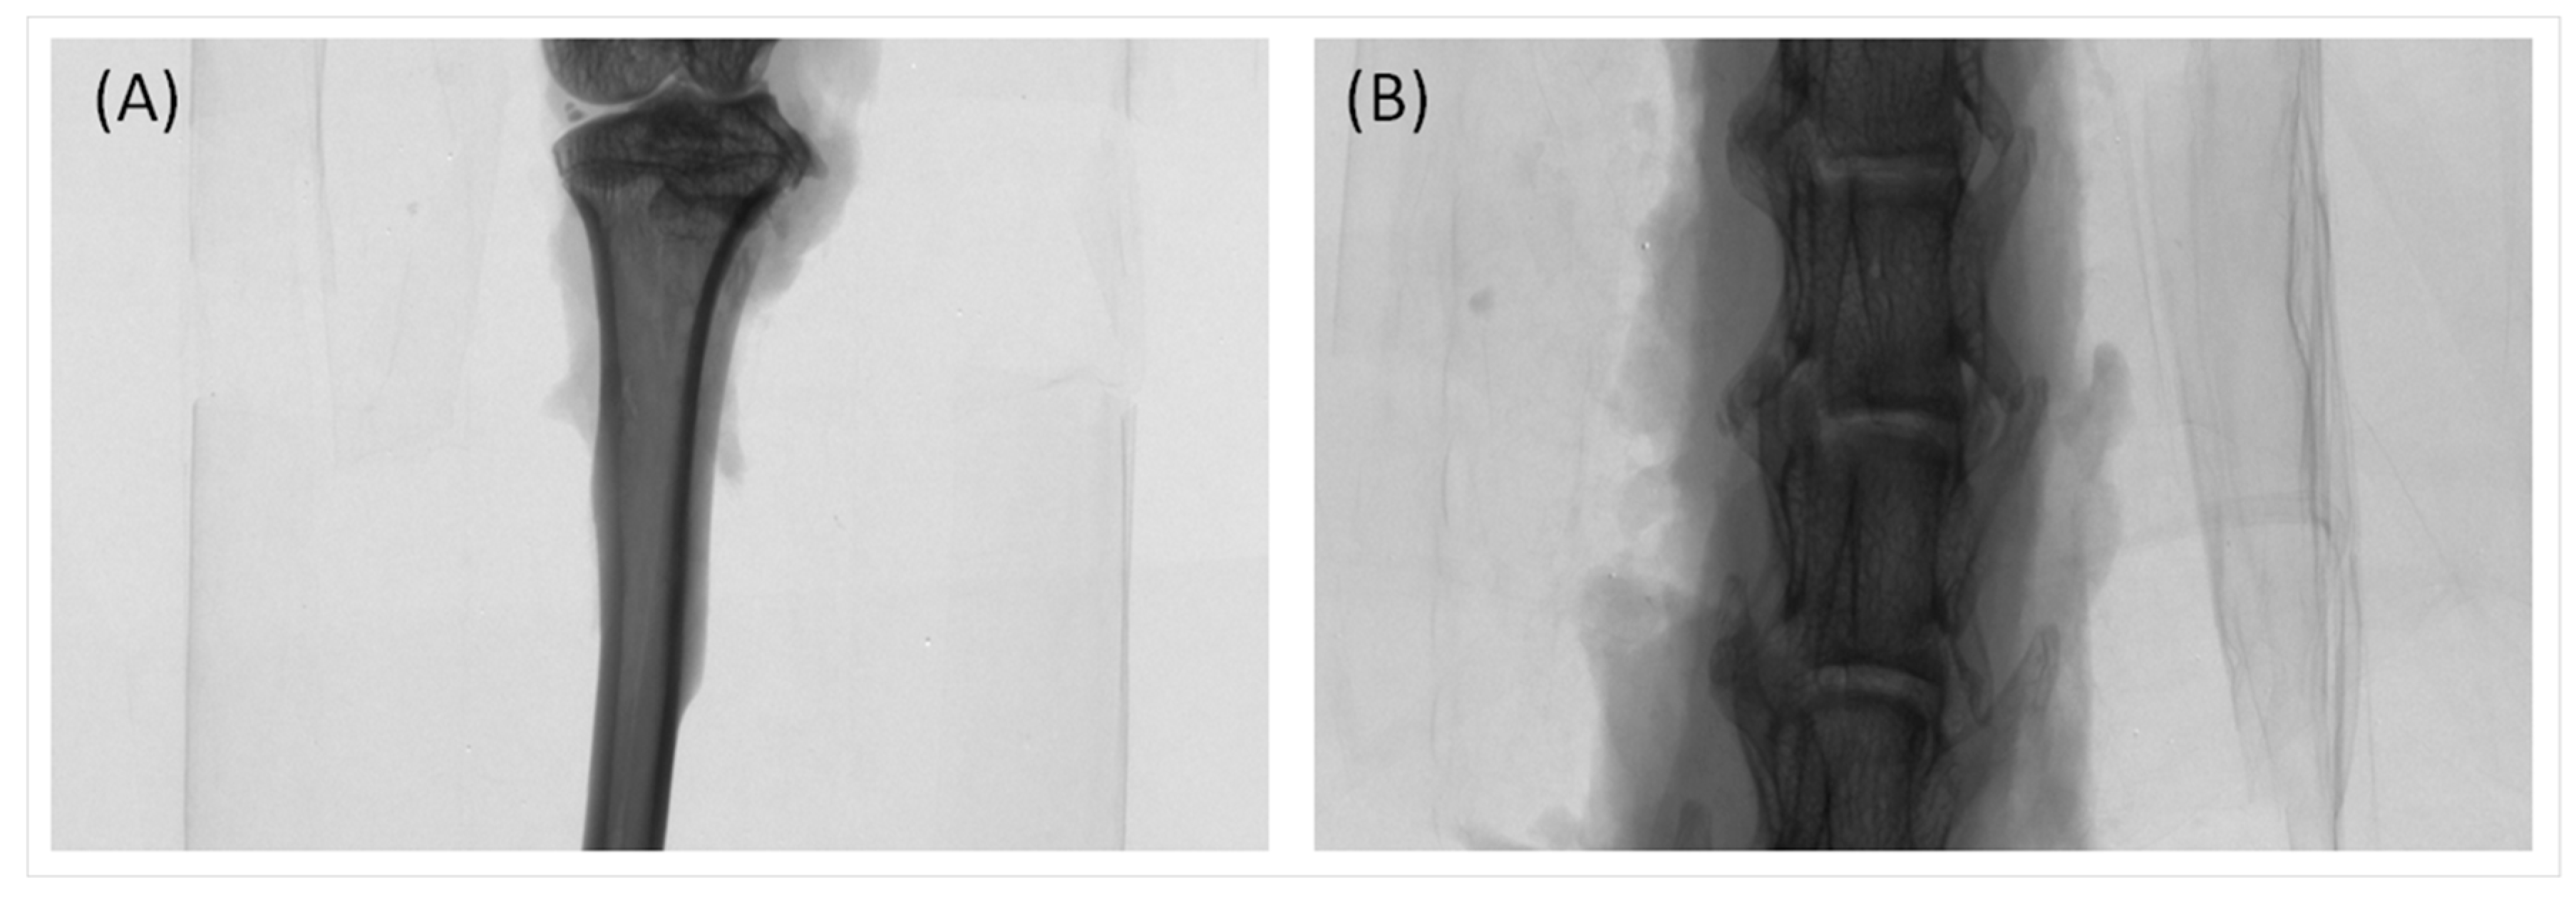

2.2. Trabecular Bone Analysis (Tibia)

| Tibia | I-OVX | I-0.05PRP | I-0.5PRP | I-0.05PRP/L | I-0.5PRP/L | S-OVX | S-0.5PRP | S-0.05PRP/L | S-0.5PRP/L |

|---|---|---|---|---|---|---|---|---|---|

| BV/TV, % | 4.07 (0.45) | 3.41 (0.69) | 3.27 (0.41) | 9.00 a (2.04) | 2.61 (0.39) | 3.78 (0.80) | 5.65 (0.63) | 7.60 (2.01) | 4.77 (0.79) |

| TbTh, mm | 0.10 (0.00) | 0.10 (0.00) | 0.10 (0.01) | 0.11 (0.00) | 0.10 (0.00) | 0.11 (0.01) | 0.11 (0.00) | 0.12 (0.01) | 0.11 (0.01) |

| TbN, mm−1 | 0.41 (0.05) | 0.29 (0.05) | 0.32 (0.04) | 0.81 a (0.19) | 0.27 (0.04) | 0.41 (0.09) | 0.53 (0.07) | 0.68 (0.19) | 0.45 (0.08) |

| TbSp, mm | 1.10 (0.11) | 1.16 (0.07) | 1.22 (0.13) | 1.04 (0.14) | 1.26 (0.08) | 1.26 (0.22) | 1.09 (0.12) | 1.09 (0.22) | 1.35 (0.16) |